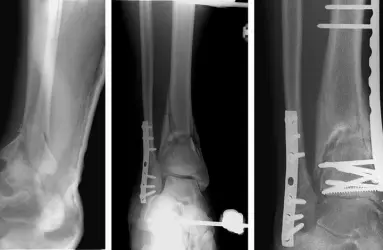

- Düztabanlık (Pes Planus)

- Ayak Başparmak Çıkıntısı (Halluks Valgus)